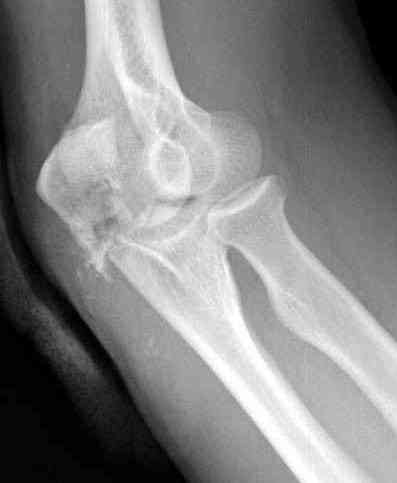

Здесь выставлены несколько случаев и варианты фиксации локтевого

отростка, некоторые в комбинации с другими переломами.

Вложение не в текстовом формате было извлечено…

Имя     : 3 olecranon prelim fixation 3.jpg

Тип     : image/jpeg

Размер  : 17512 байтов

Описание: отсутствует

Url     : http://weborto.net:8080/pipermail/ortho/attachments/20071121/9a993135/attachment-0008.jpg